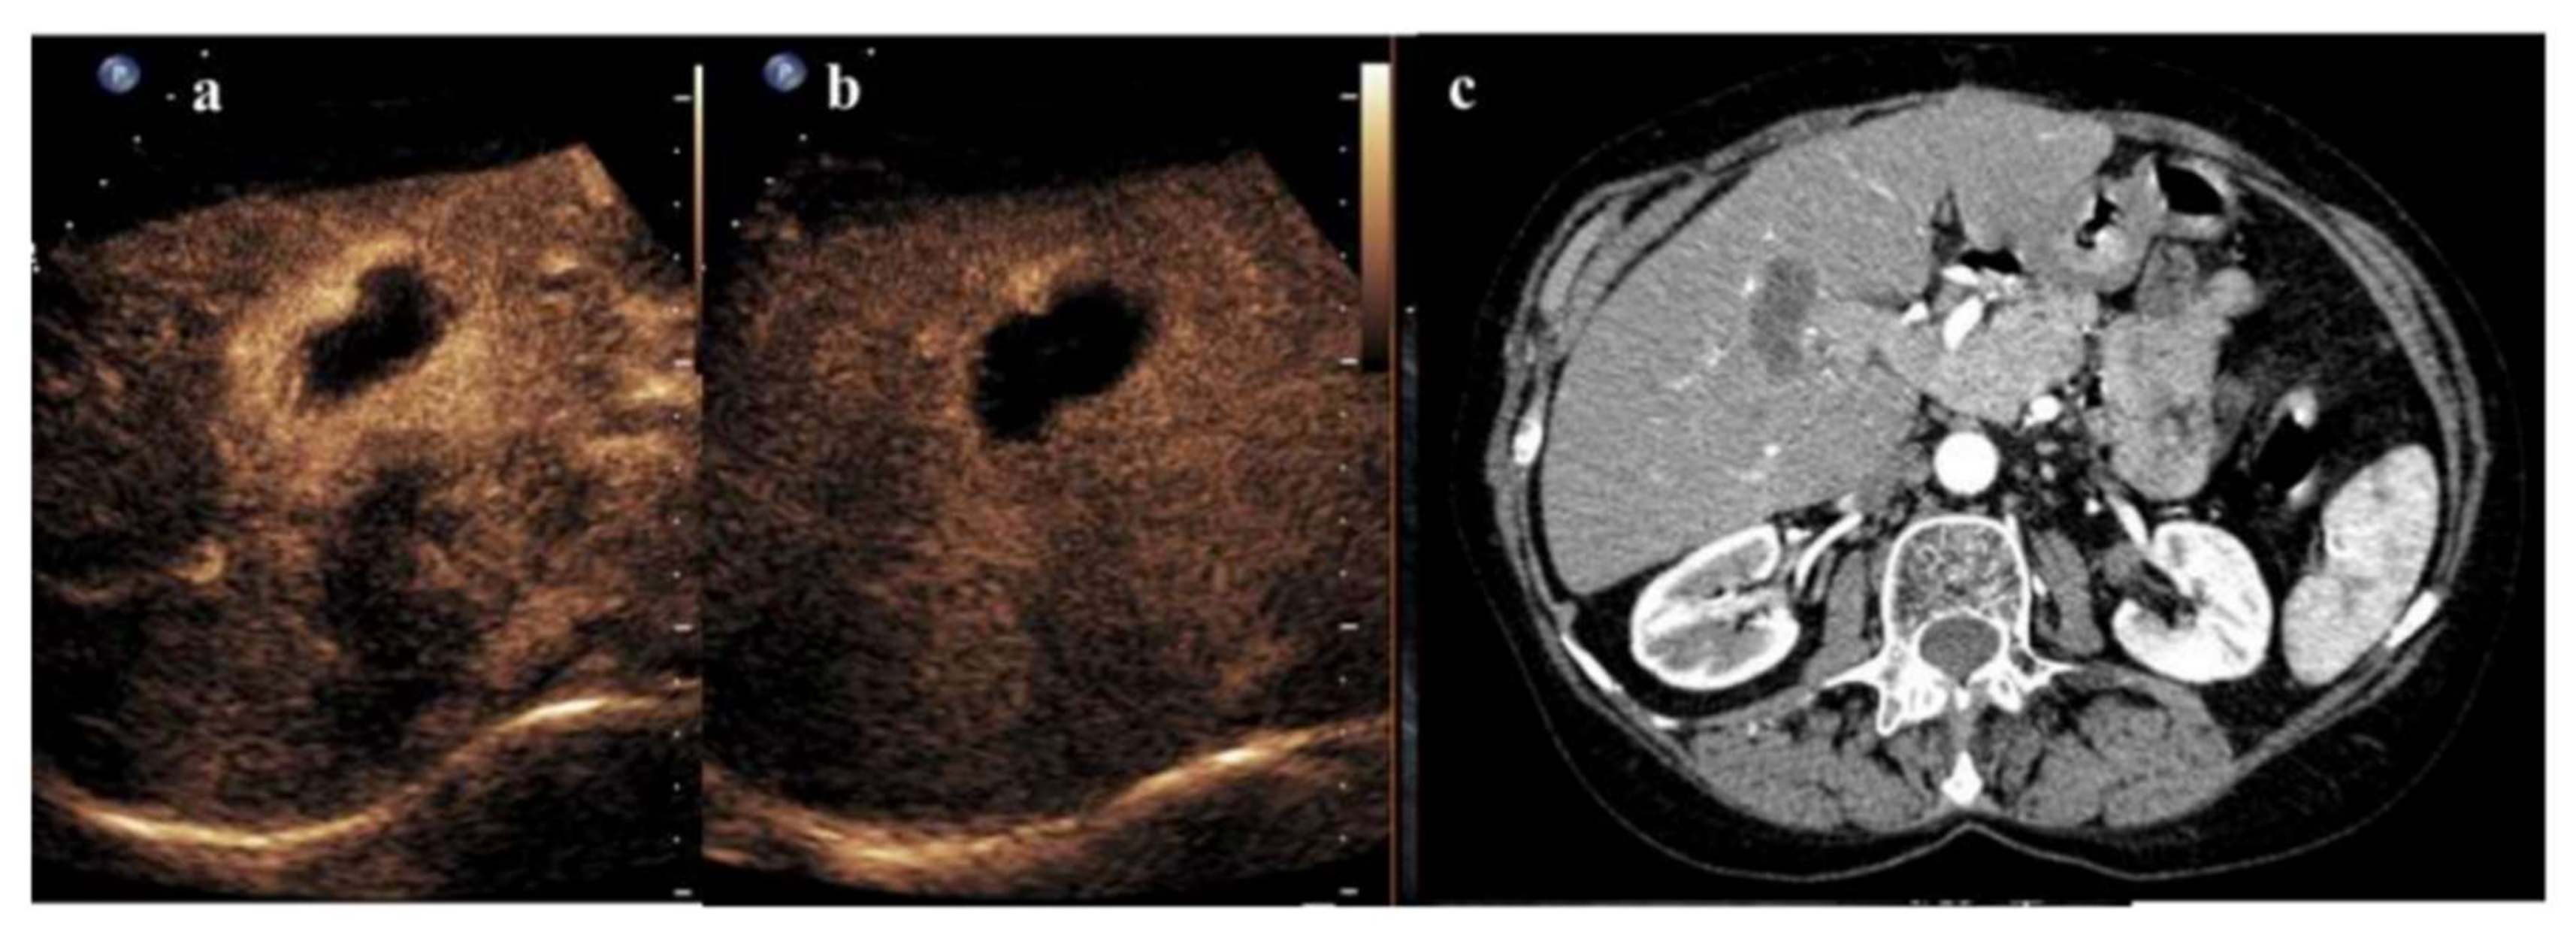

3. Radiofrequency Ablation and CEUS

- Ricci, P.; Cantisani, V.; Drudi, F.; Pagliara, E.; Bezzi, M.; Meloni, F.; Calliada, F.; Erturk, S.M.; D’Andrea, V.; D’Ambrosio, U.; et al. Is contrast-enhanced US alternative to spiral CT in the assessment of treatment outcome of radiofrequency ablation in hepatocellular carcinoma? Ultraschall Med. Eur. J. Ultrasound 2009, 30, 252–258. [Google Scholar] [CrossRef] [Green Version]

- Lu, M.D.; Yu, X.L.; Li, A.H.; Jiang, T.A.; Chen, M.H.; Zhao, B.Z.; Zhou, X.D.; Wang, J.R. Comparison of contrast enhanced ultrasound and contrast enhanced CT or MRI in monitoring percutaneous thermal ablation procedure in patients with hepatocellular carcinoma: A multi-center study in China. Ultrasound Med. Biol. 2007, 33, 1736–1749. [Google Scholar] [CrossRef] [PubMed]

- Zheng, S.G.; Xu, H.X.; Lu, M.D.; Xie, X.Y.; Xu, Z.F.; Liu, G.J.; Liu, L.N. Role of contrast-enhanced ultrasound in follow-up assessment after ablation for hepatocellular carcinoma. World J. Gastroenterol. 2013, 19, 855–865. [Google Scholar] [CrossRef]

- Dill-Macky, M.J.; Asch, M.; Burns, P.; Wilson, S. Radiofrequency ablation of hepatocellular carcinoma: Predicting success using contrast-enhanced sonography. Am. J. Roentgenol. 2006, 186 (Suppl. S5), S287–S295. [Google Scholar] [CrossRef] [PubMed]

- Meloni, M.F.; Andreano, A.; Franza, E.; Passamonti, M.; Lazzaroni, S. Contrast enhanced ultrasound: Should it play a role in immediate evaluation of liver tumors following thermal ablation? Eur. J. Radiol. 2012, 81, e897–e902. [Google Scholar] [CrossRef]

- Ainora, M.E.; Iezzi, R.; Ponziani, F.R.; Garcovich, M.; Di Stasio, E.; Riccardi, L.; Annicchiarico, B.E.; Abbate, V.; De Gaetano, A.M.; Siciliano, M.; et al. Contrast-Enhanced Ultrasound in the Short-Term Evaluation of Hepatocellular Carcinoma after Locoregional Treatment. Dig. Dis. 2020, 38, 522–533. [Google Scholar] [CrossRef] [PubMed]